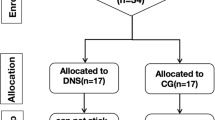

With IRB approval, we collected in-clinic motion analysis and outcomes data from patients during routine clinical visits. This study includes NS-LBP patients and SD-LBP patients. NS-LBP patients had at least 6 months of LBP symptoms and no clear underlying condition responsible for pain symptoms. SD-LBP patients also had at least 6 months of LBP symptoms, but also had spinal deformity conditions including adult degenerative scoliosis and hyperkyphosis and presented sagittal imbalance of at least 40 mm on standing radiography. Subjects were excluded if they had pain or dysfunction in the cervical spine or thoracic spinal regions. Additionally, subjects were excluded if they had unrelated pain or dysfunction in the lower extremities. All of the subjects were able to walk independently and perform an unassisted STS maneuver.

This study examines 86 subjects, including 44 NS-LBP patients (mean age: 54.1 ± 17.4) and 42 SD-LBP patients (mean age: 62.9 ± 11.9; Table 1). For the two patient groups pooled, mean VAS was 5.69 (± 2.84), and mean ODI was 50.0 (± 16.2). Mean VAS was significantly lower for the NS-LBP group (4.62 ± 2.36) compared to the SD-LBP group (6.91 ± 2.89; p < 0.001). Mean ODI was not significantly different between the NS-LBP (50.7 ± 16.5) and SD-LBP (49.1 ± 16.1) groups.